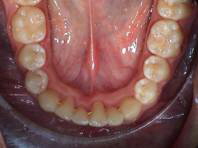

Comparación del modelo inicial con el diagnóstico tras un tratamiento activo, una vez quitadas las bandas:

Diagnóstico inicial: Estenodoncia extrema en la parte frontal de la mandíbula con escalonamiento. Invasión de las zonas de apoyo. Supraoclusión traumática. Inclinación hacia delante de la parte frontal del maxilar superior con 16 mm de escalón sagital.

|

Diagnóstico tras el tratamiento activo: Oclusión neutral, escalón sagital de sólo 2 mm. No es necesaria la extracción. Estabilización con un retenedor lingual permanente.